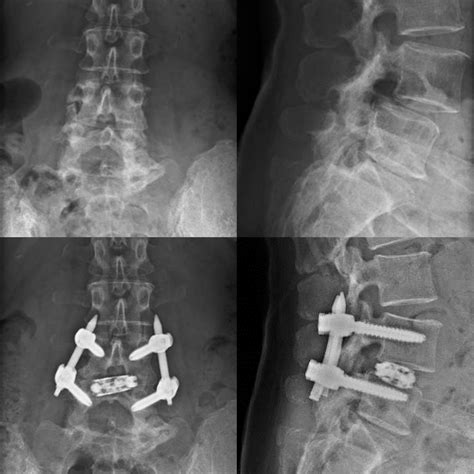

• Bone Grafting: Bone graft material is placed between the L4 and L5 vertebrae to promote fusion.

• Instrumentation: Screws, rods, or cages may be used to stabilize the vertebrae and hold them in place while the fusion heals.

A Fused L4 and L5 procedure involves surgically joining the L4 and L5 vertebrae to eliminate movement between them. This is typically done to alleviate pain caused by conditions that affect the discs or vertebrae in this region. The fusion process can be achieved through various techniques, including: